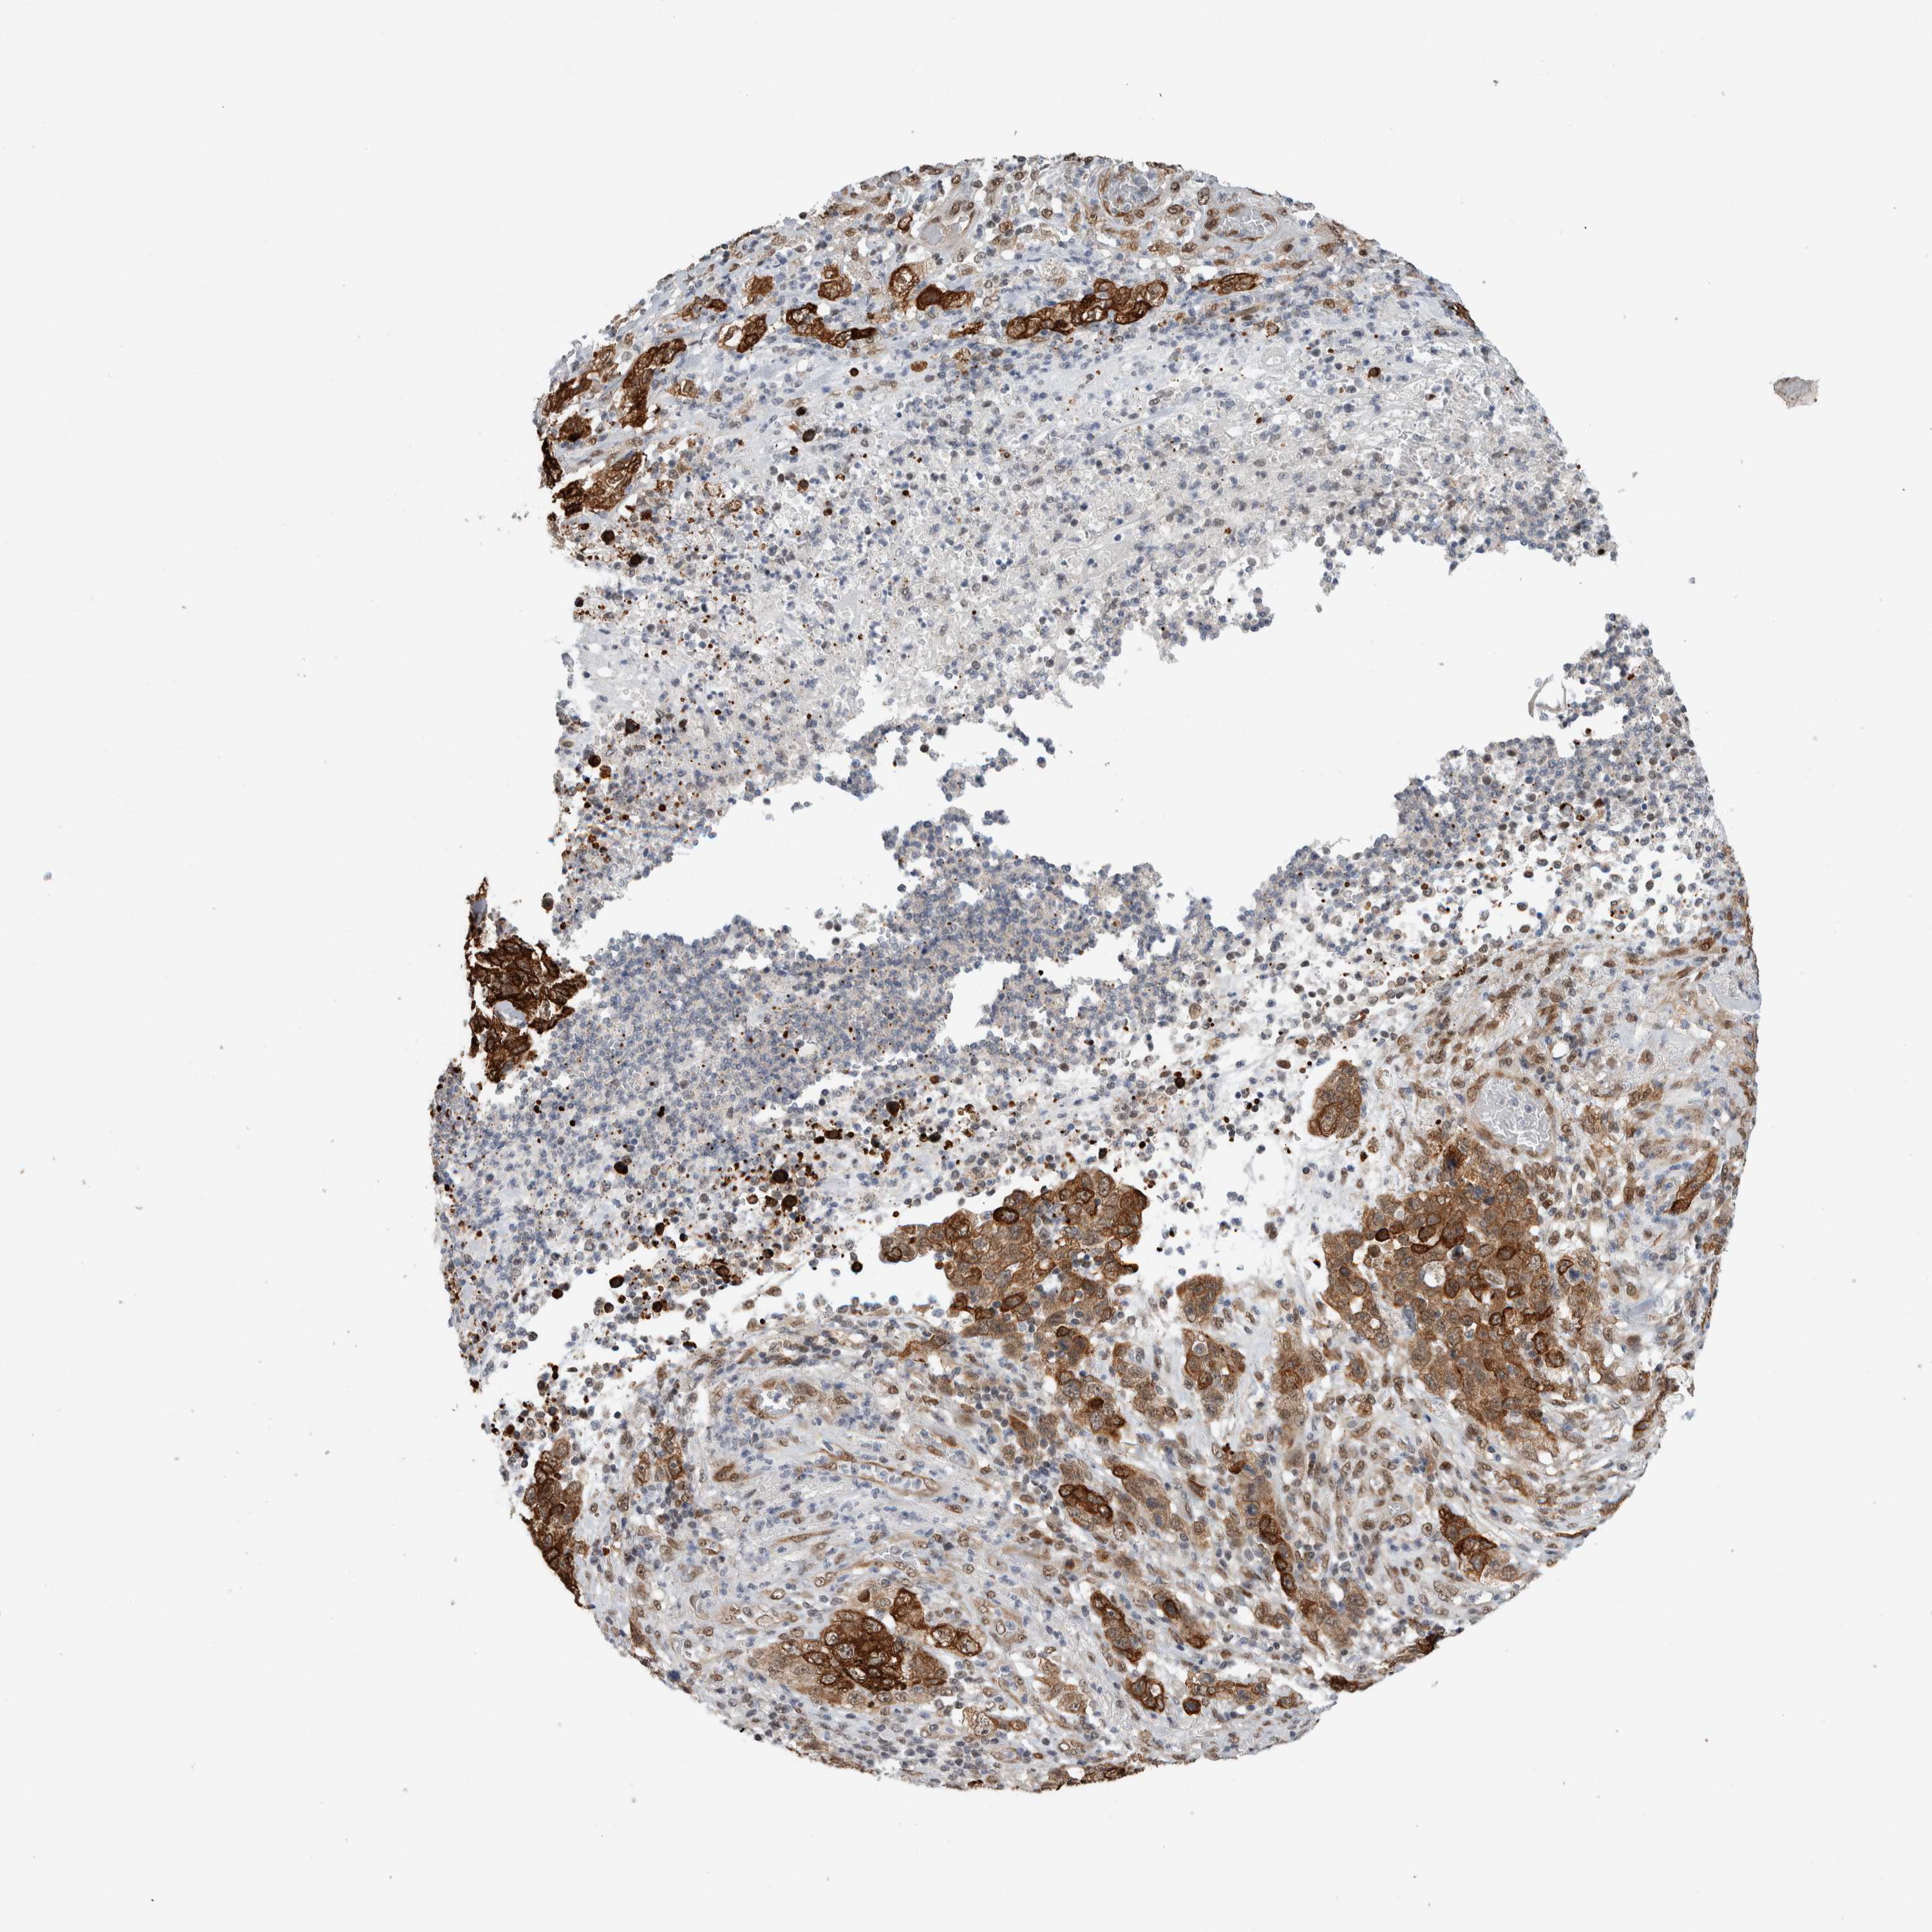

STOMACH CANCER - Protein expressioni

A mouse-over function shows sample information and annotation data. Click on an image to view it in a full screen mode. Samples can be filtered based on level of antibody staining by selecting one or several of the following categories: high, medium, low and not detected. The assay and annotation is described here.

Note that samples used for immunohistochemistry by the Human Protein Atlas do not correspond to samples in the TCGA dataset.

Antibody stainingi

Antibody staining in the annotated cell types in the current human tissue is reported as not detected, low, medium, or high, based on conventional immunohistochemistry profiling in selected tissues. This score is based on the combination of the staining intensity and fraction of stained cells.

Each image is clickable and will lead to virtual microscopy that enables deeper exploration of all samples and also displays staining intensity scores, fraction scores and subcellular localization as well as patient and tissue information for each sample.

Antibody HPA020730

Antibody HPA024251

Staining

High

Medium

Low

Not detected

Intensity

Strong

Moderate

Weak

Negative

Quantity

>75%

75%-25%

<25%

None

Location

Nuclear

Cytoplasmic/membranous

Cytoplasmic/membranous,nuclear

Adenocarcinoma, NOS